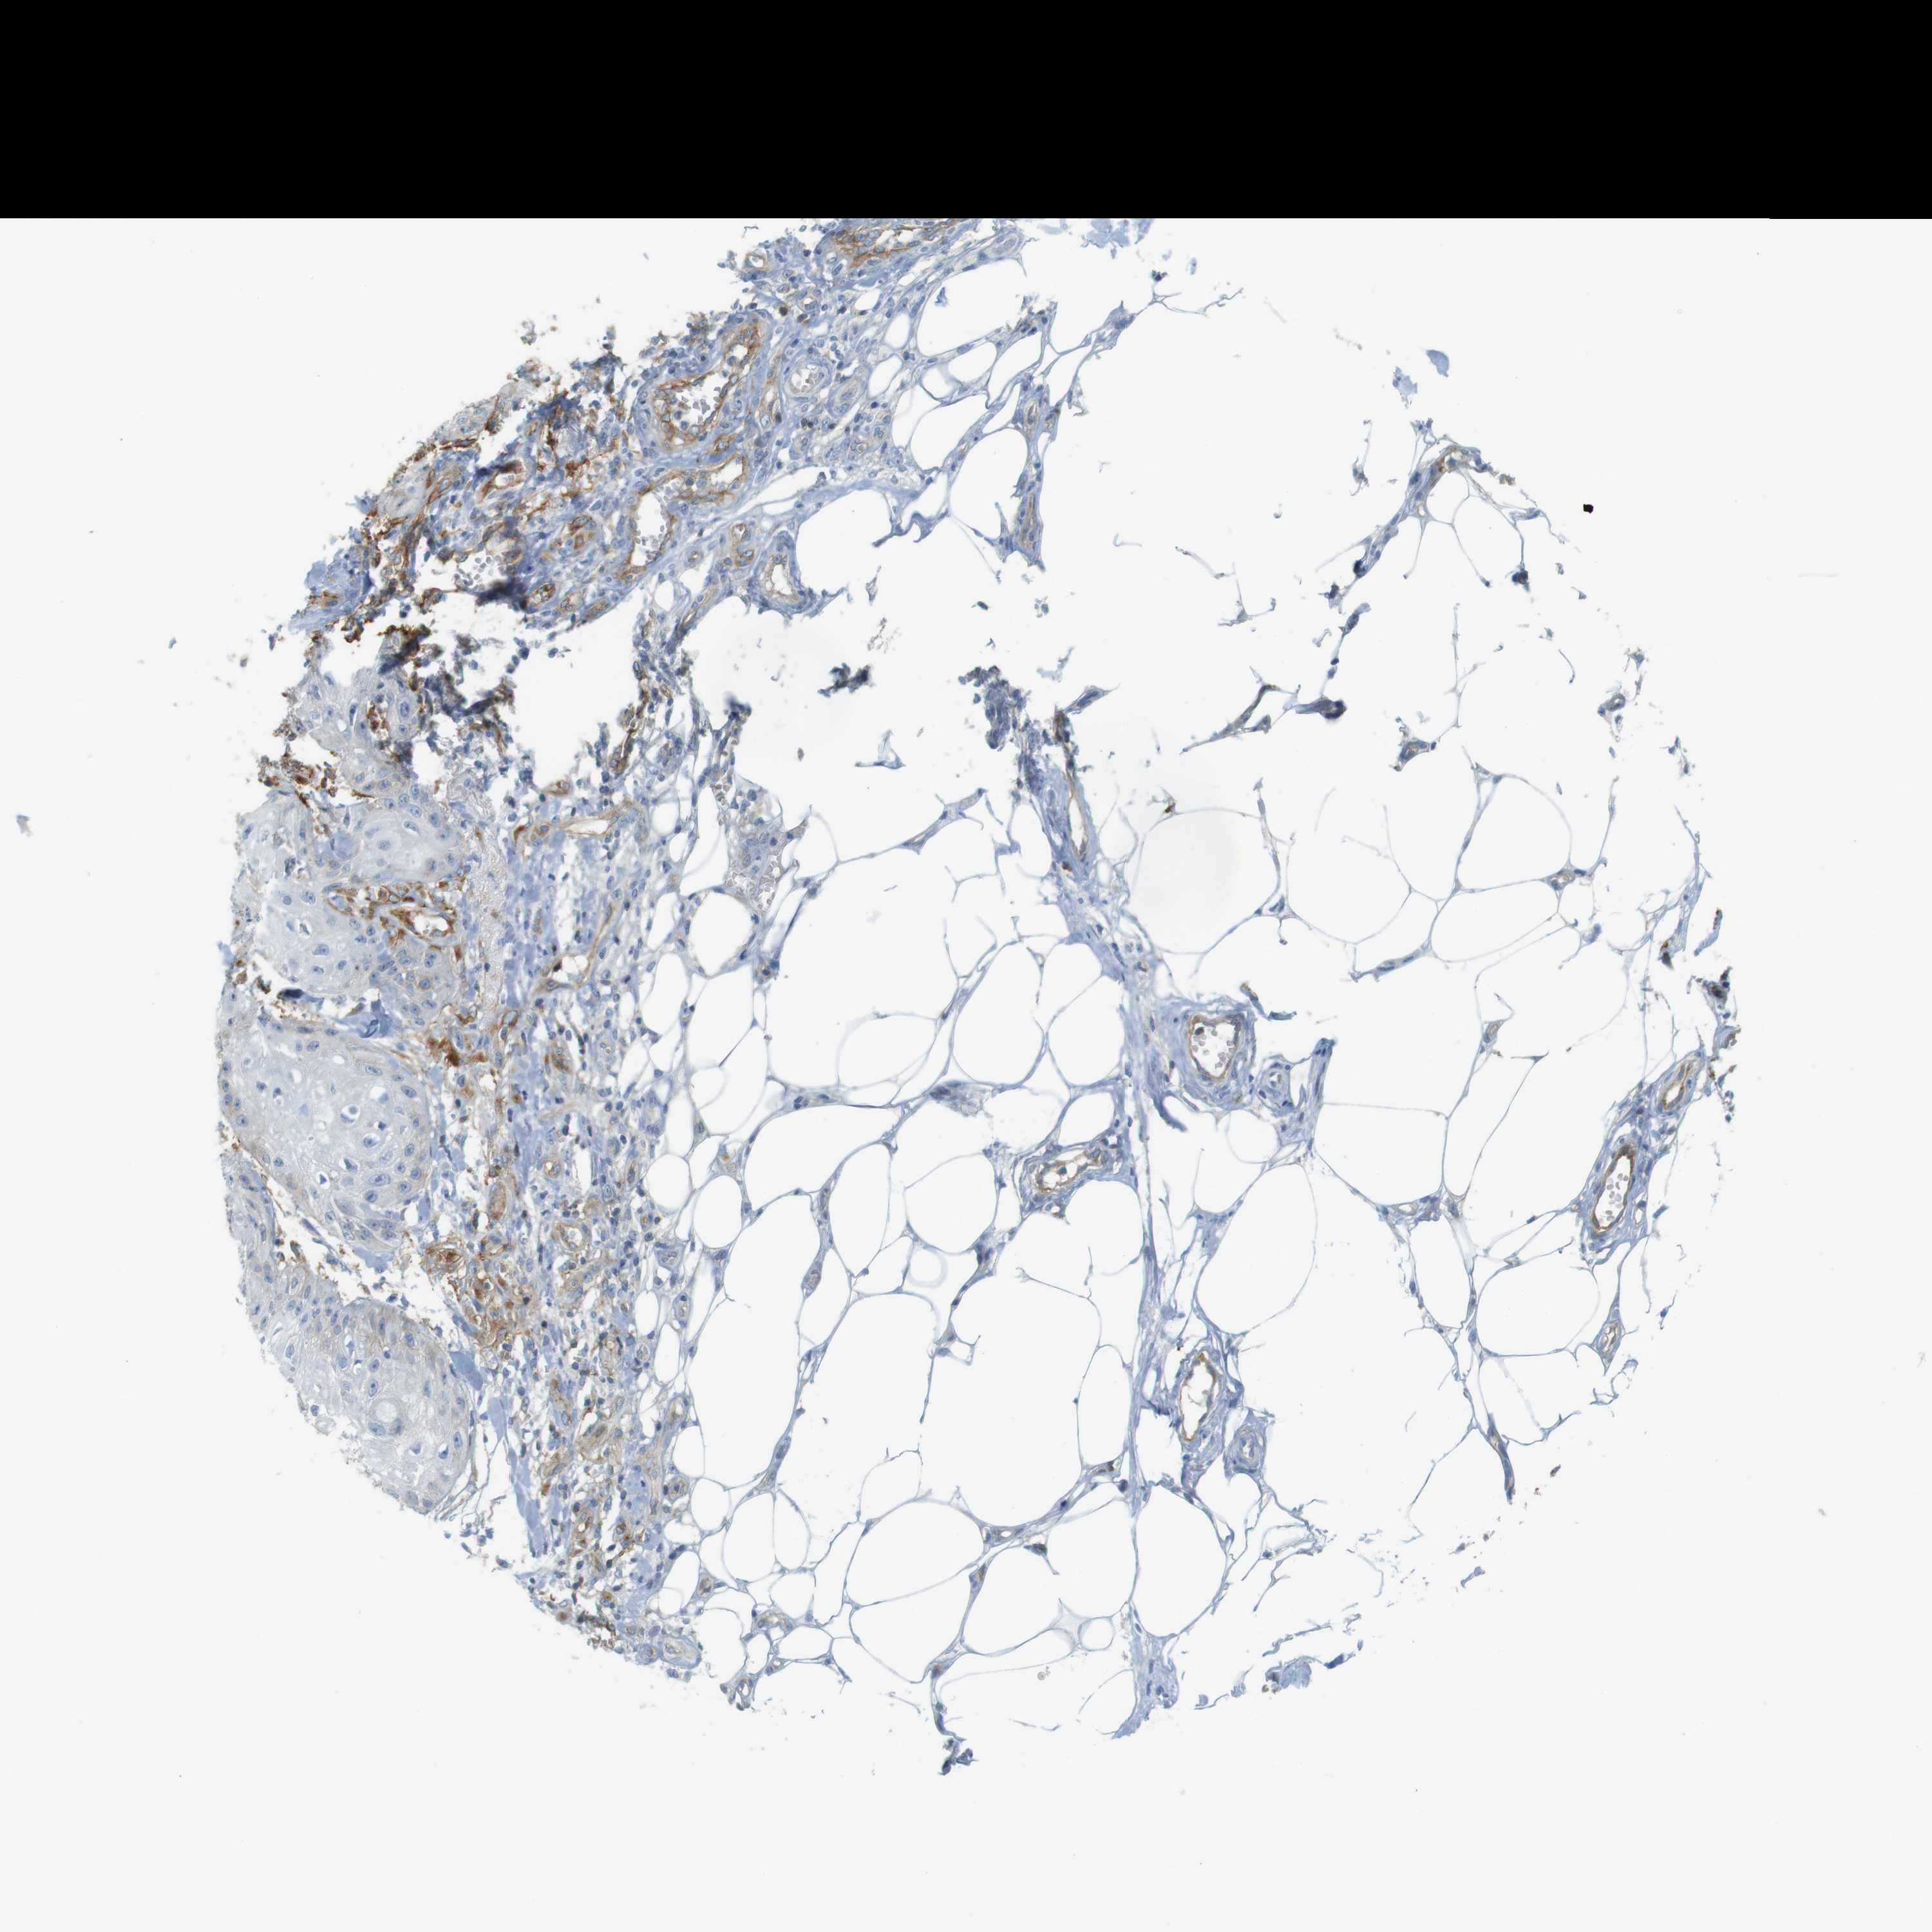

SKIN CANCER - Protein expressioni

A mouse-over function shows sample information and annotation data. Click on an image to view it in a full screen mode. Samples can be filtered based on level of antibody staining by selecting one or several of the following categories: high, medium, low and not detected. The assay and annotation is described here.

Antibody stainingi

Antibody staining in the annotated cell types in the current human tissue is reported as not detected, low, medium, or high, based on conventional immunohistochemistry profiling in selected tissues. This score is based on the combination of the staining intensity and fraction of stained cells.

Each image is clickable and will lead to virtual microscopy that enables deeper exploration of all samples and also displays staining intensity scores, fraction scores and subcellular localization as well as patient and tissue information for each sample.

Antibody CAB008973

Antibody CAB012962

Staining

High

Medium

Low

Not detected

Intensity

Strong

Moderate

Weak

Negative

Quantity

>75%

75%-25%

<25%

None

Location

Nuclear

Cytoplasmic/membranous

Cytoplasmic/membranous,nuclear

Basal cell carcinoma